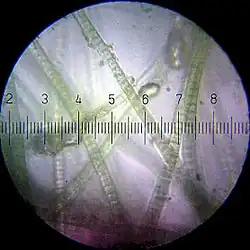

2- Cyanobacteria

Cyanobacteria contain neurotoxin named BMAA(β-N-methylamino-L-alanine). BMAA was verified that is strongly poisonous to animal nerve cells, increasing the speed of deterioration of animal brain cells. Accumulation of small amounts of BMAA can kill all brain nerve cells of rat.